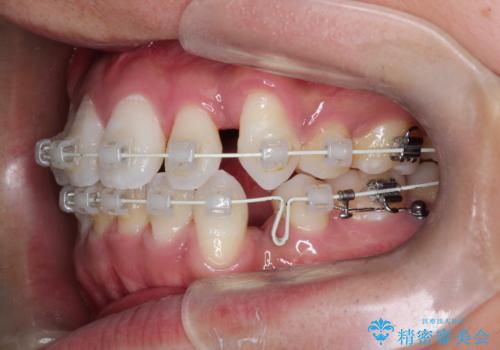

非抜歯で無理に並べようとすると、歯列が外側に広がり、前歯が前方に突き出て口元が突出してしまうリスクがありました。患者様の「これ以上前歯を外に出したくない」という強いご希望を重視し、上下左右の4番目の歯(第一小臼歯)を計4本抜歯してスペースを確保する計画を立案。装置は、装置の見た目を考慮し、白く目立ちにくい審美ワイヤーを選択しました。

抜歯によって作られたスペースを利用し、前歯を後方に維持したまま、ガタついている歯を一つひとつ正しい位置へと整列させていきました。

審美ワイヤーを用いることで、歯の根元から角度を精密にコントロールし、前歯が前方に傾斜するのを防ぎながらスペースを閉じていきました。これにより、口元のボリュームを維持したまま、美しいアーチ状の歯並びを構築することが可能となりました。